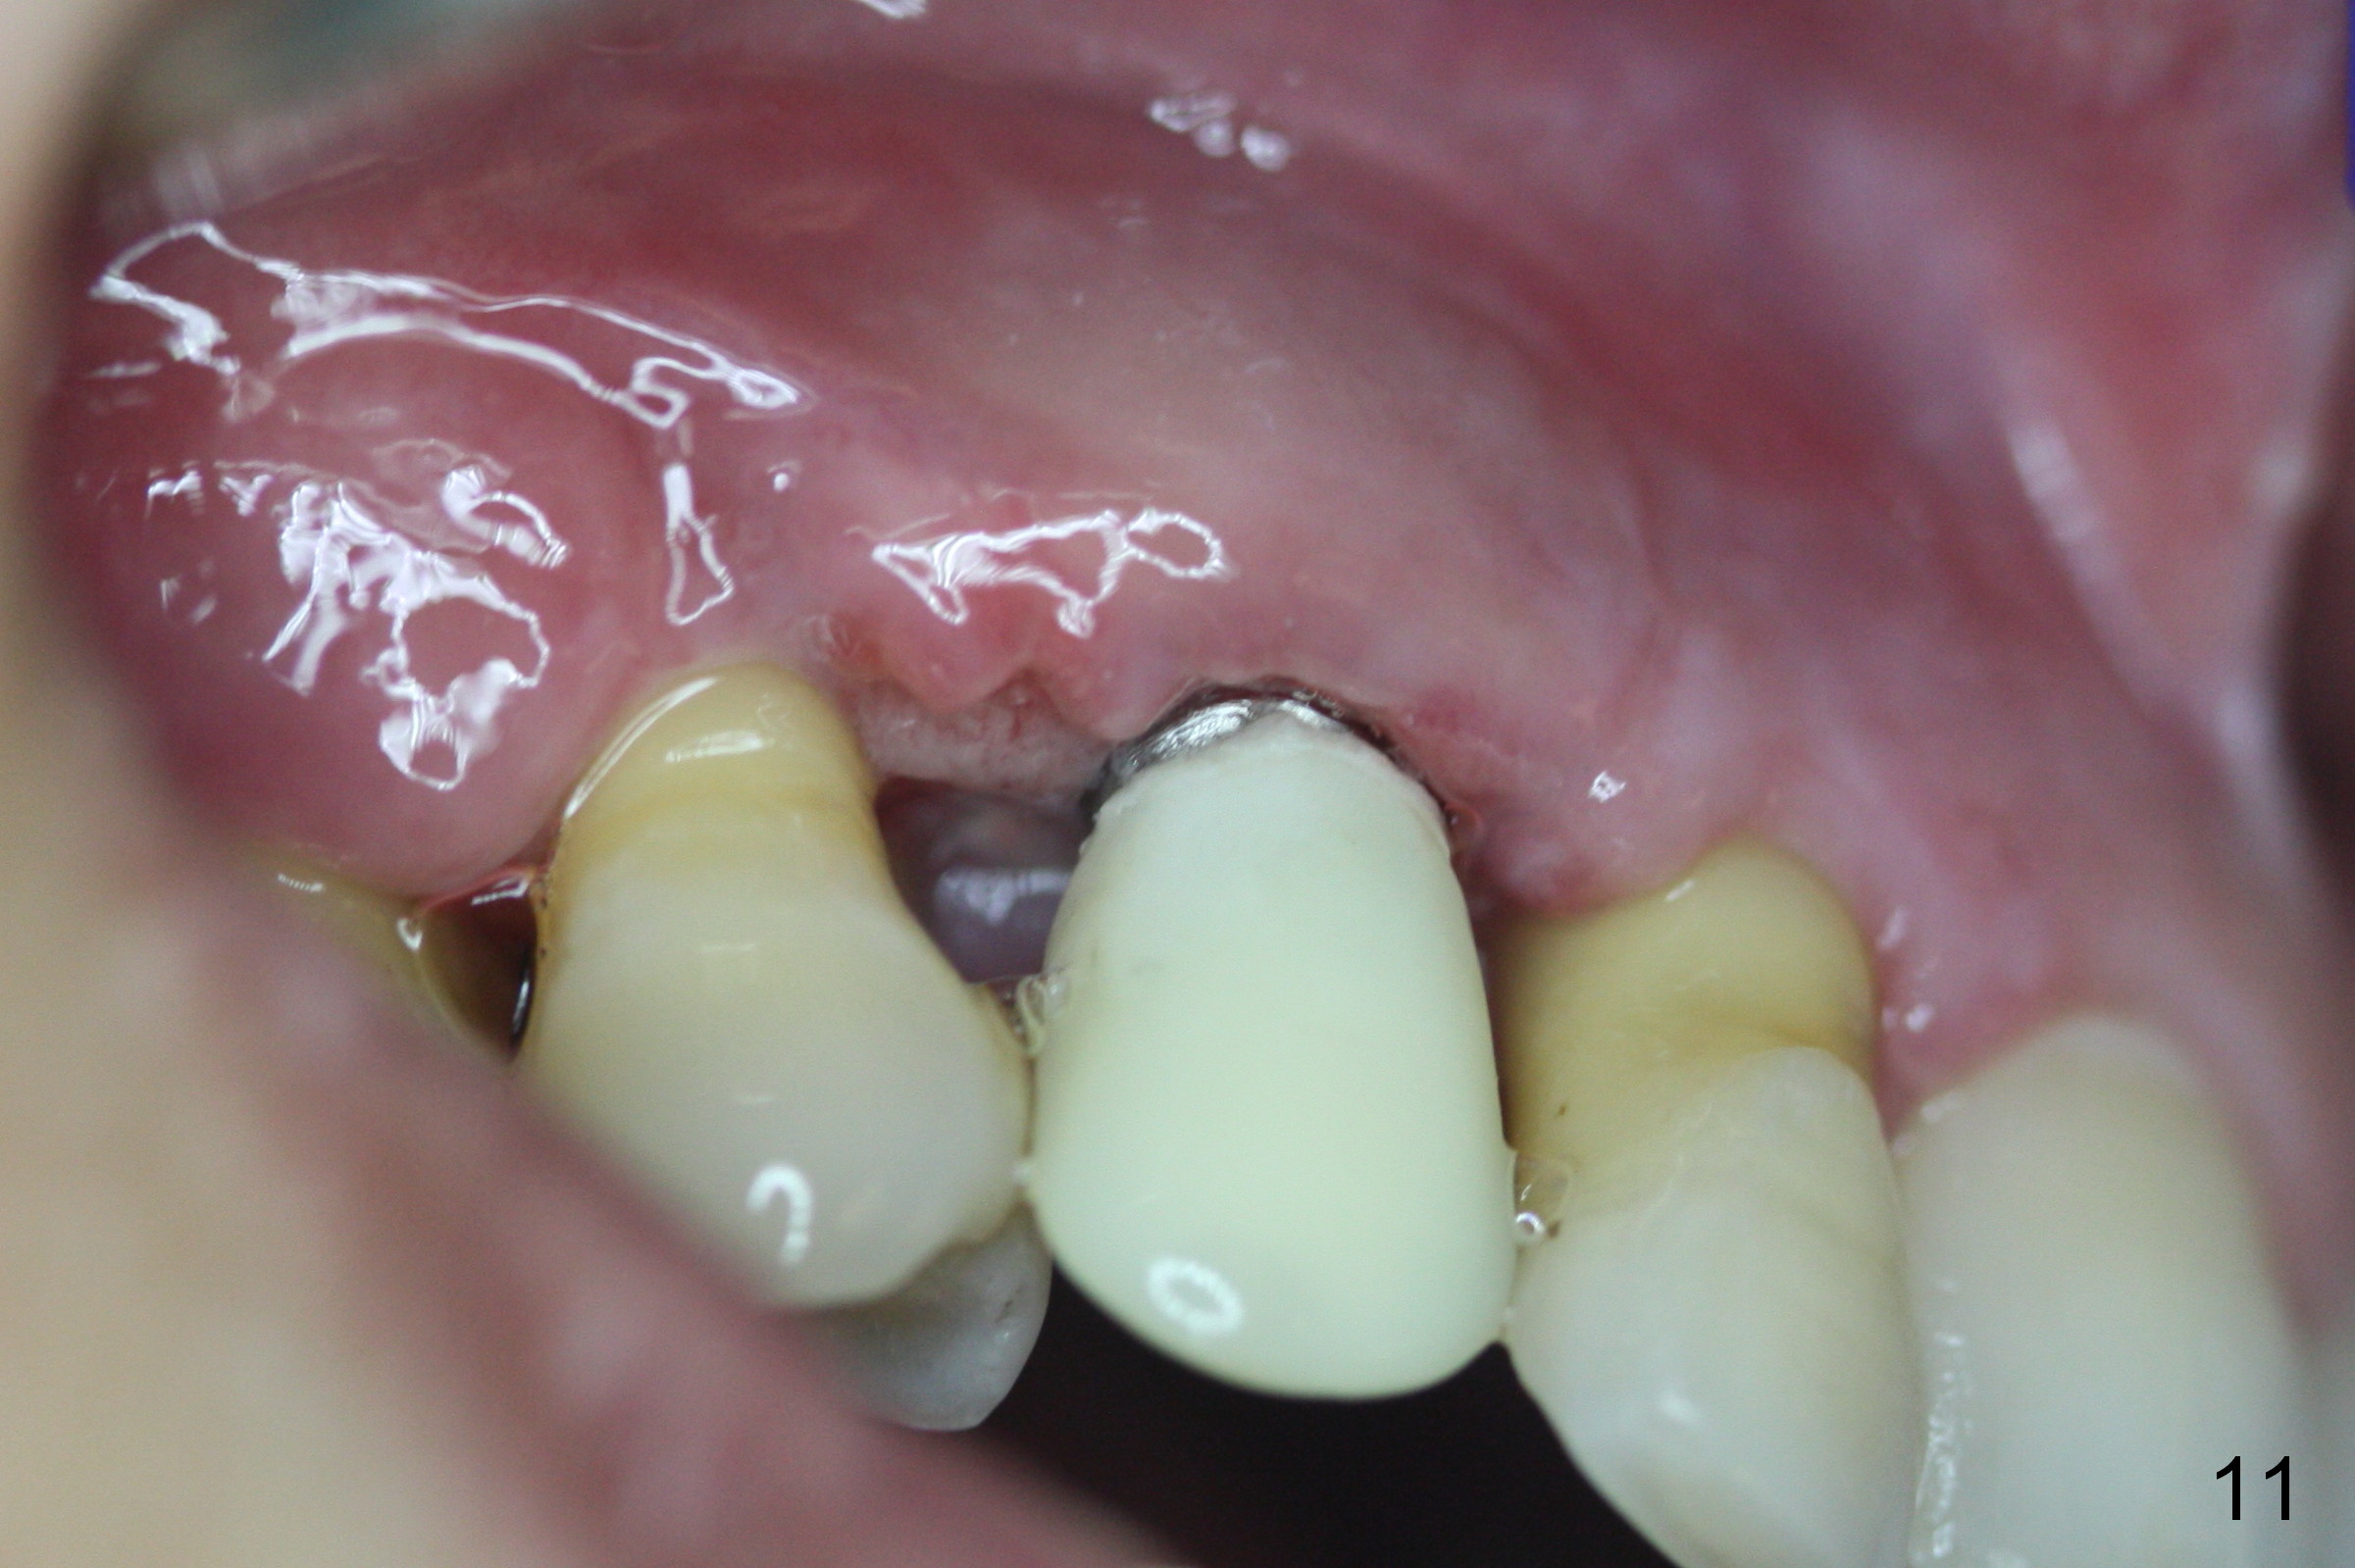

Four months post implant placement, the immediate provisional (Fig.1 P) has mobility with tenderness and perforation at the cervix (^). When the provisional is removed, the buccal plate bulging is more evident (Fig.2 arrowheads). The latter is apparently caused by bone expansion associated with implant placement (Fig.3 black *), since the bulging is not so obvious in a preop CBCT 3 D image (Fig.4 *). There is a layer of fiber granulation tissue (Fig.3 white *) around the mobile implant (I). More fiber tissue is noted when the implant is removed (Fig.5). A new osteotomy is created in the palatal wall of the existing implant site with 2 mm pilot drill, followed by 2.5 and 3 mm reamers. As a 4.5x17 mm tap is being inserted (Fig.6 T), it is deviated buccally. Reamers are re-used to try to remove more palatal bone to let the implant be placed more palatally. When a 4.5x17 mm tissue-level implant is placed (Fig.7,8 I with insertion torque >60 Ncm), there is a small buccal gap (Fig.8 *). A 20° angled abutment (Fig.7,8 A) is placed. An immediate provisional is fabricated with cosmetic satisfaction.